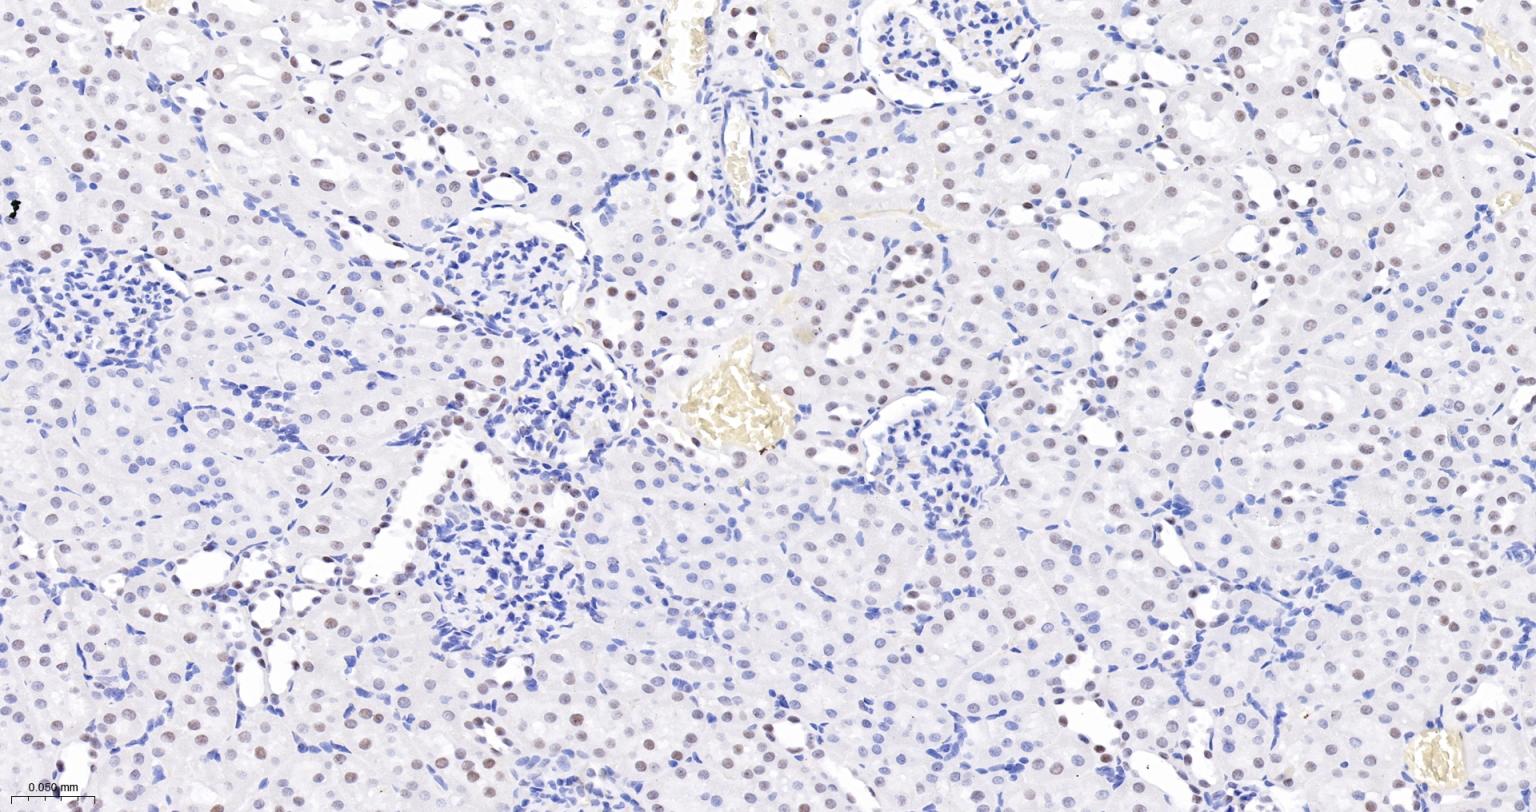

Paraformaldehyde-fixed, paraffin embedded Rat Lung; Antigen retrieval by boiling in sodium citrate buffer (pH6.0) for 15 min; The section was incubated with USP39 Monoclonal Antibody, Unconjugated (bsm-63016R) at 1:200 overnight at 4°C, followed by conjugation to the bs-0295G-HRP and DAB (C-0010) staining.